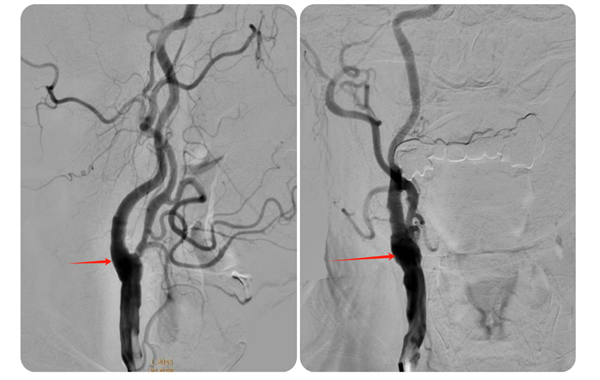

▲术前脑血管造影

针对何先生的病情,捆绑调教 神经外科脑血管病团队迅速制定了治疗方案,决定采用颈动脉内膜剥脱术为其进行治疗。手术过程中,林通副主任医师及其团队成功帮助何先生剥离了颈动脉内膜上的黄色硬斑块,恢复了血管的通畅。

术后,何先生顺利苏醒,回到神经外科病房进行监护治疗,术后7天伤口愈合良好拆线出院。8月何先生来捆绑调教 复查,DSA检查提示右侧颈动脉狭窄已完全恢复并无再狭窄,头晕及左侧肢体乏力症状也完全缓解了。

▲术后狭窄完全解除